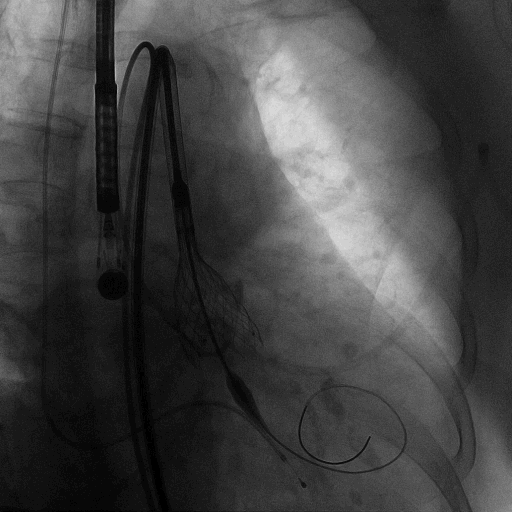

术中造影

植入L26 VenusA-Plus瓣膜,标准位释放,释放到2/3,观察瓣膜位置,以及再次确认冠脉风险,左冠正常显影,选择全部释放。

术后结果

造影可见轻微瓣周漏,与FEops预测一致。